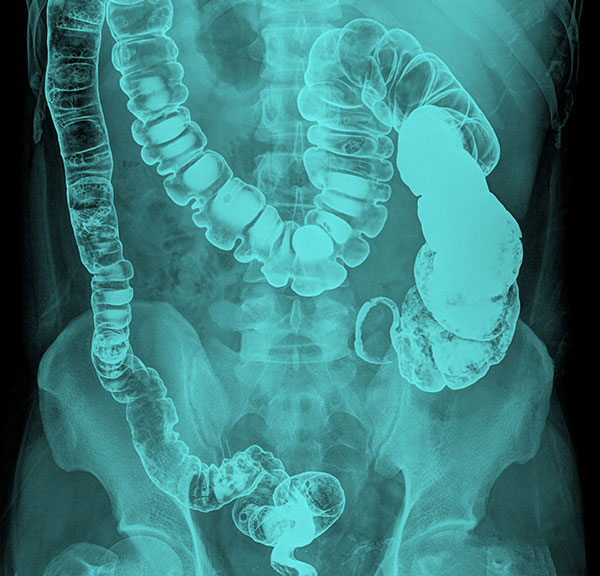

Chất tương phản bari-sulfat thì được nuốt hoặc uống để làm tăng độ tương phản hình ảnh chụp X-quang và CT của đường tiêu hóa như hầu họng, thực quản, dạ dày, ruột non và ruột già (đại tràng).

Chất tương phản đường trực tràng

Chất tương phản bari-sulfat dạng bơm thụt (đường trực tràng) được dùng để tăng độ tương phản hình ảnh chụp X-quang và CT của đường tiêu hóa dưới (đại tràng và trực tràng).